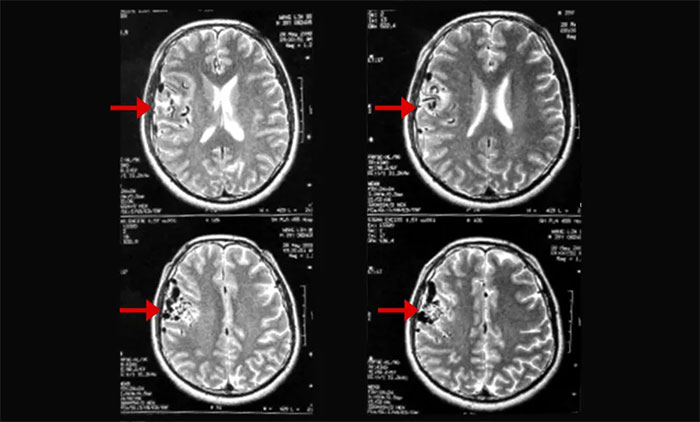

▲ 磁共振影像提示右颞顶动静脉畸形

上海蓝十字脑科医院肿瘤科(放疗)头部伽玛刀组主任陈琦曾收治一位青年男性AVM患者胡某(化名)。该患者曾因头晕头痛、口齿不清在当地医院就医,影像检查提示“右颞顶占位”,考虑为脑肿瘤可能性大,采取药物对症治疗。其后,患者因前额顶部位胀痛找到陈琦主任团队寻求进一步治疗方案。通过影像学检查,提示病灶区域潜在血管异常,诊断排除脑肿瘤,而是右颞顶动静脉畸形。